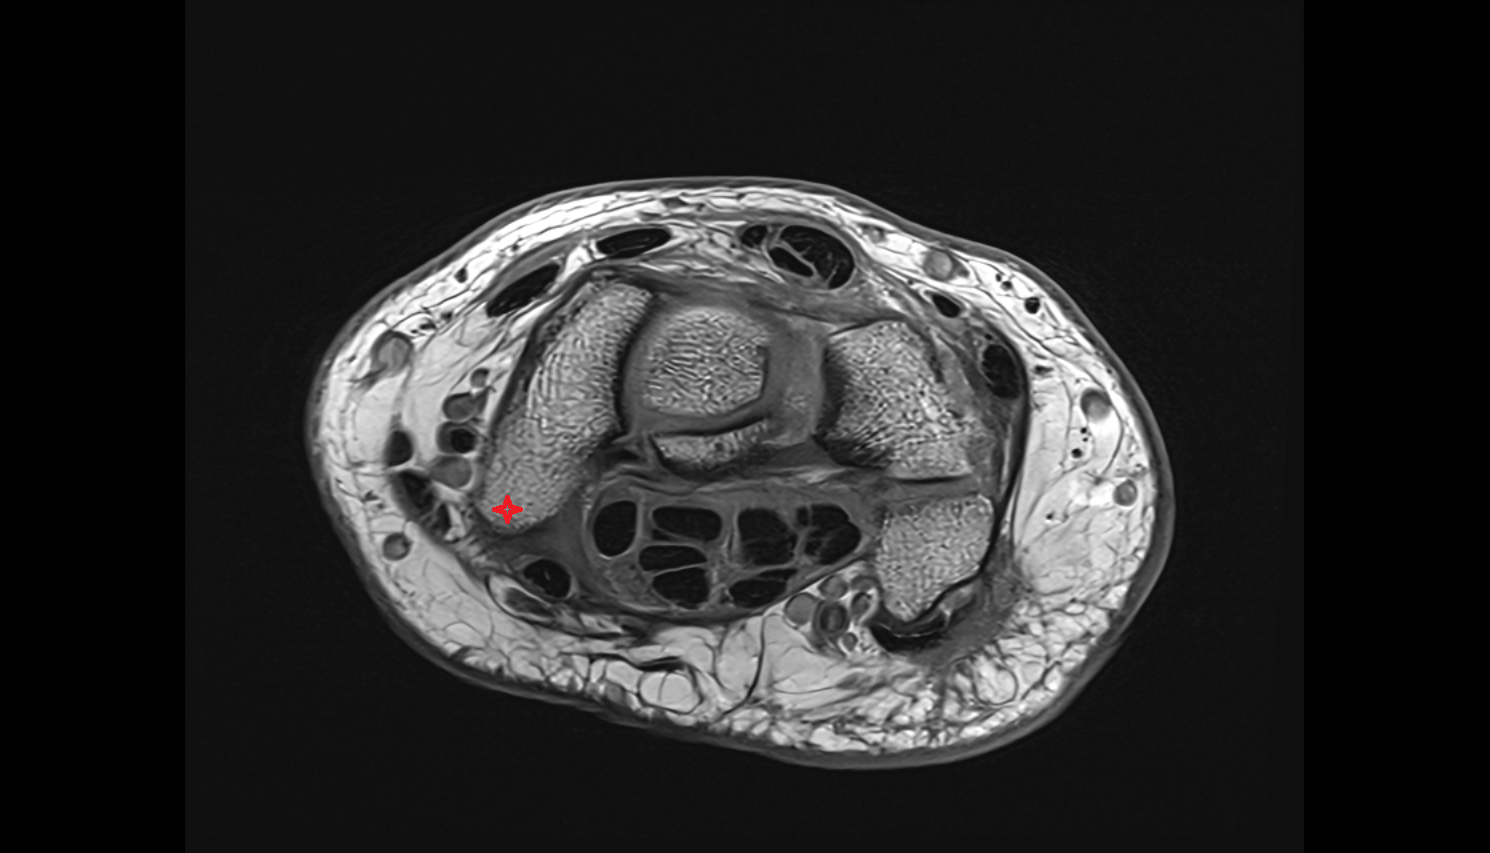

- Knee Joint

- Medial meniscus

- Lateral meniscus

- Anterior cruciate ligament

- Posterior cruciate ligament